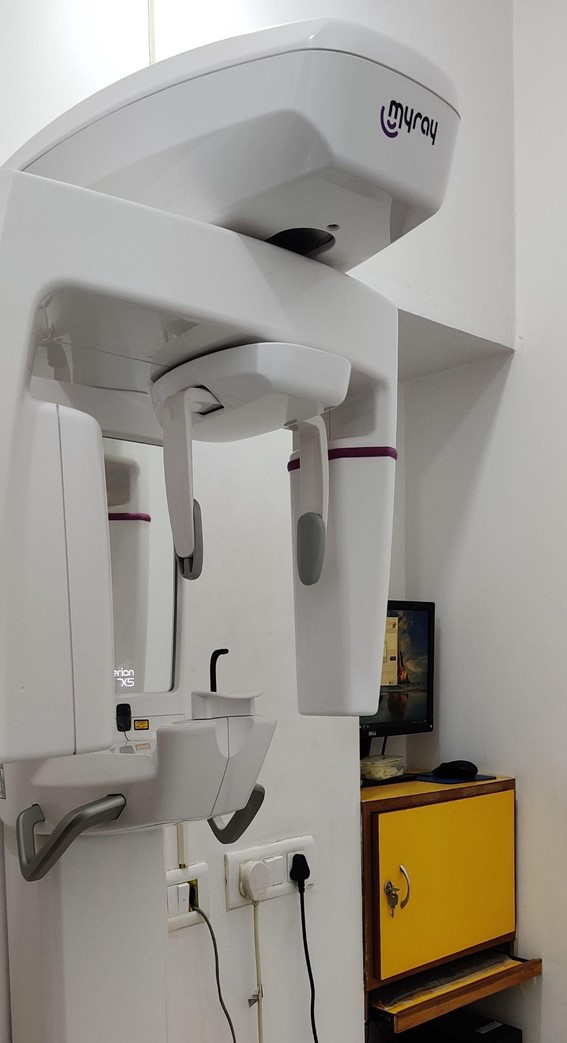

OPG Machine